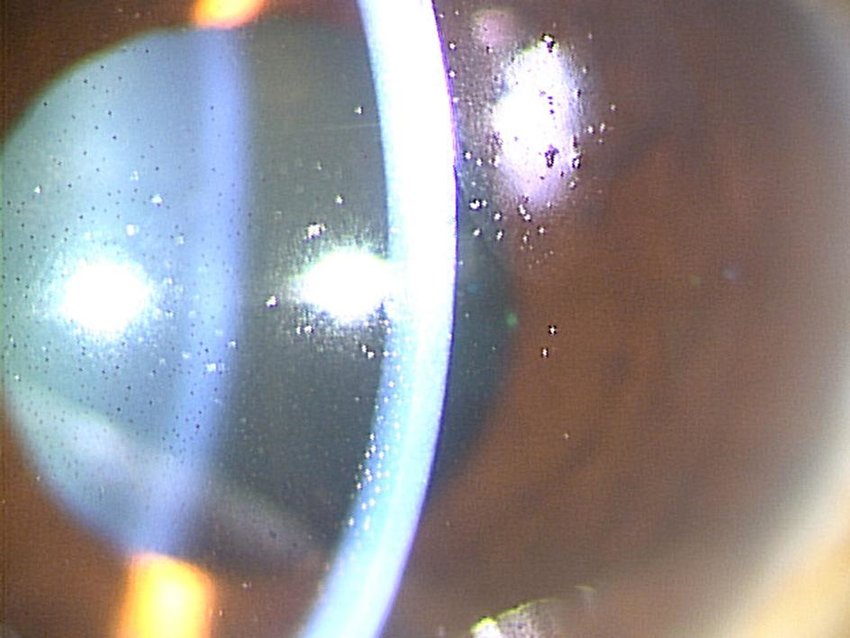

<각막함요, 각막델렌, 각막패임, dellen>

각막함요, dellen 이란

각막 윤부 주위에 불룩튀어난 융기된 병변 혹은 윤부 주위에 염증이 발생하였을 때,

그 인접한 각막부분에서 패임이 발생하여, 눈물층이 각막위에 고이는 현상을 말합니다.

여과포가 윤부주위에 위치하게되다보니, 융기된 여과포가 있을 때,

눈을 깜박이거나, 움직일 때 각막 눈물층의 국소적 파괴로 인해 각막 델렌이 발생합니다.

대부분은 인공누액점안과 안대로 치료됩니다.